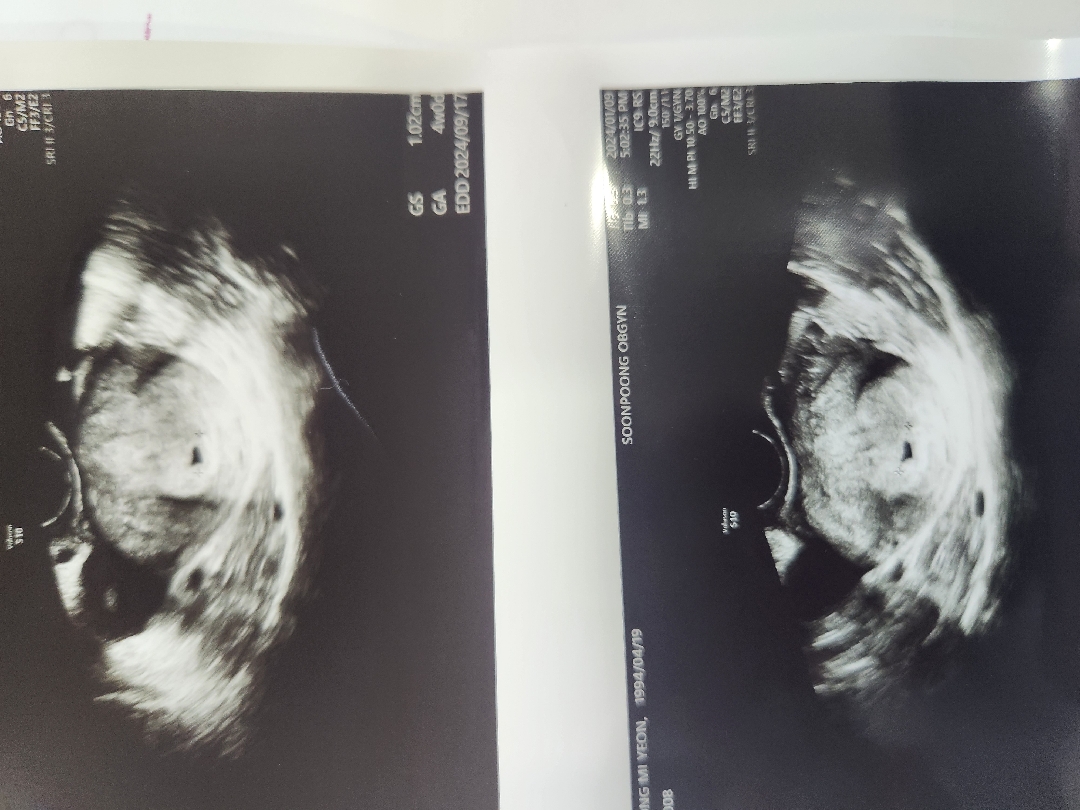

아기집❤️

저번주에 못보고 1주일동안 자궁외임신일까봐 걱정많이하고 스트레스도받았는데 열심히만들어놨네요 4주2일입니당~ 출산예정일은 9월15일!! 6월15일이 결혼식인데 정확히 3개월뒤네요 다이어트는 어찌해야할지ㅠ